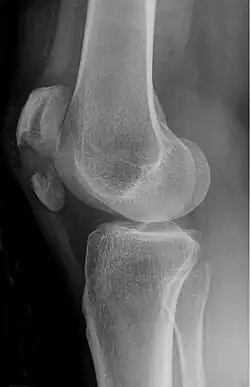

The patella can break in various ways depending on the way it is injured, and into two or more pieces.[1] Types include transverse, the most common, with one fracture line;[5] marginal; osteochondral; and the rare vertical type, or stellate, where a direct compression force gives rise to a comminuted pattern.[5][7] Patella fractures can be further classified as displaced, where the broken ends of bone do not line up correctly and separate by more than 2mm, or undisplaced and stable where pieces of bone remain in contact with each other.[1][7] If fragments of patella bone stick out from the skin it is known as an open patella fracture, and closed if the overlying skin is intact.[1]

Transverse fracture of patella -